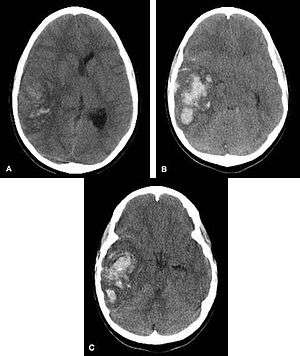

In the elderly population, amyloid angiopathy is associated with cerebral infarcts as well as hemorrhage in superficial locations, rather than deep white matter or basal ganglia. These are usually described as "lobar". These bleedings are not associated with systemic amyloidosis.

Hemorrhagic neoplasms are more complex, heterogeneous bleeds often with associated edema. These hemorrhages are related to tumor necrosis, vascular invasion and neovascularity. Glioblastomas are the most common primary malignancies to hemorrhage while thyroid, renal cell carcinoma, melanoma, and lung cancer are the most common causes of hemorrhage from metastatic disease.

Other causes of intraparenchymal hemorrhage include hemorrhagic transformation of infarction which is usually in a classic vascular distribution and is seen in approximately 24 to 48 hours following the ischemic event. This hemorrhage rarely extends into the ventricular system.